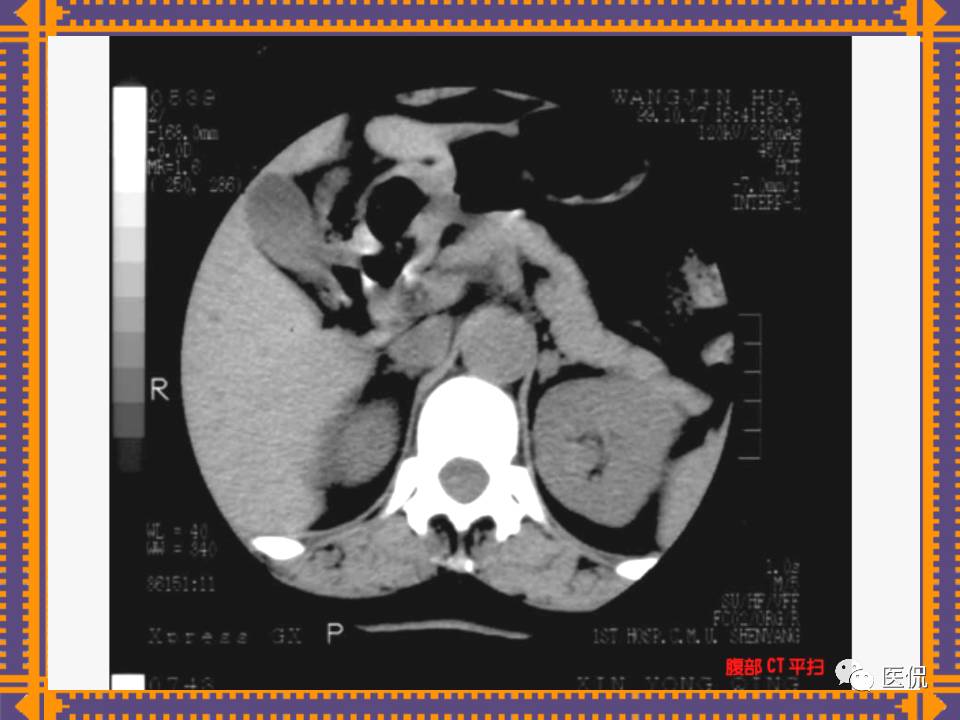

这篇PPT对男性生殖系统疾病:前列腺增生、前列腺癌;女性生殖系统疾病:子宫肌瘤、子宫癌、卵巢囊肿和卵巢肿瘤以及腹膜后间隙疾病进行了详细讲解。